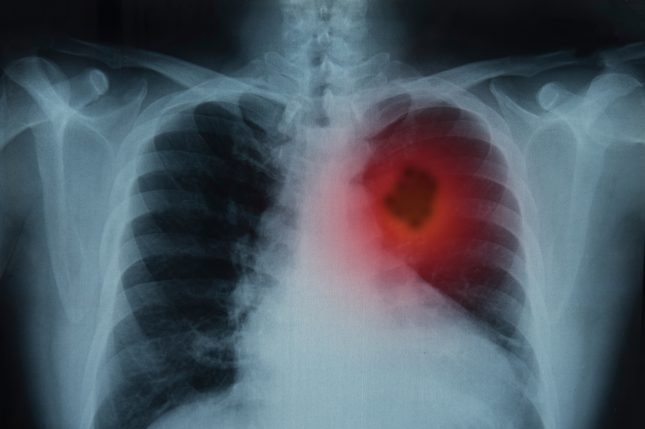

בשני מחקר פאזה 3 הודגם כי ניבולומאב, תרופה המעכבת את PD-1, משפרת שרידות כללית לעומת דוקסטקסל במטופלים עם NSCLC מתקדם, קשקשי ושאינו קשקשי, שקיבלו טיפול קודם. במחקר המתואר כאן, החוקרים מדווחים על מעקב של חמש שנים ממחקר פאזה 1 שבמסגרתו אוכלוסיית מטופלים זו קיבלה ניבולומאב.

החוקרים מצאו כי שיעור השרידות הכוללת המשוער לחמש שנים היה 16% עבור כלל המשתתפים שקיבלו טיפול (129 משתתפים). שיעור השרידות הכללית לחמש שנים היה דומה עבור NSCLC קשקשי (16%) ושאינו קשקשי (15%). מתוך 16 המשתתפים ששרדו לאחר חמש שנים, 88% היו מעשנים בהווה או בעבר. מתוך 10 משתתפים ששרדו לאחר חמש שנים עם ביטוי PD-L1 הניתן למדידה ל-70% היה ביטוי השווה או גדול מ-1% בתחילת המחקר. מתוך המשתתפים ששרדו לאחר חמש שנים, 81% קיבלו מעל לקו טיפול אחד לפני תחילת המחקר.

75% מהשורדים לאחר חמש שנים השיגו תגובה חלקית לניבולומאב לפי קריטריוני RECIST v1.0. ל-12% מהמשתתפים היתה מחלה יציבה ול-12% היתה התקדמות מחלה. תשעה שורדים לאחר חמש שנים (56%) השלימו 96 שבועות של טיפול עם ניבולומאב, ארבעה (25%) הפסיקו בשל תופעות לוואי ושלושה (19%) בגלל התקדמות מחלה. נכון לזמן ניתוח הנתונים עבור עבודה זו, 75% מהשורדים לאחר חמש שנים לא נזקקו לטיפול נוסף והיו ללא עדות להתקדמות מחלה.

החוקרים מסכמים כי ניבולומאב מובילה לשרידות כוללת ארוכת טווח ולתגובה ממושכת בשיעור ניכר של מטופלים עם NSCLC שטופל קודם לכן. למטופלים ששרדו לאחר חמש שנים היו מגוון רחב של מאפייני בסיס ומאפייני טיפול.